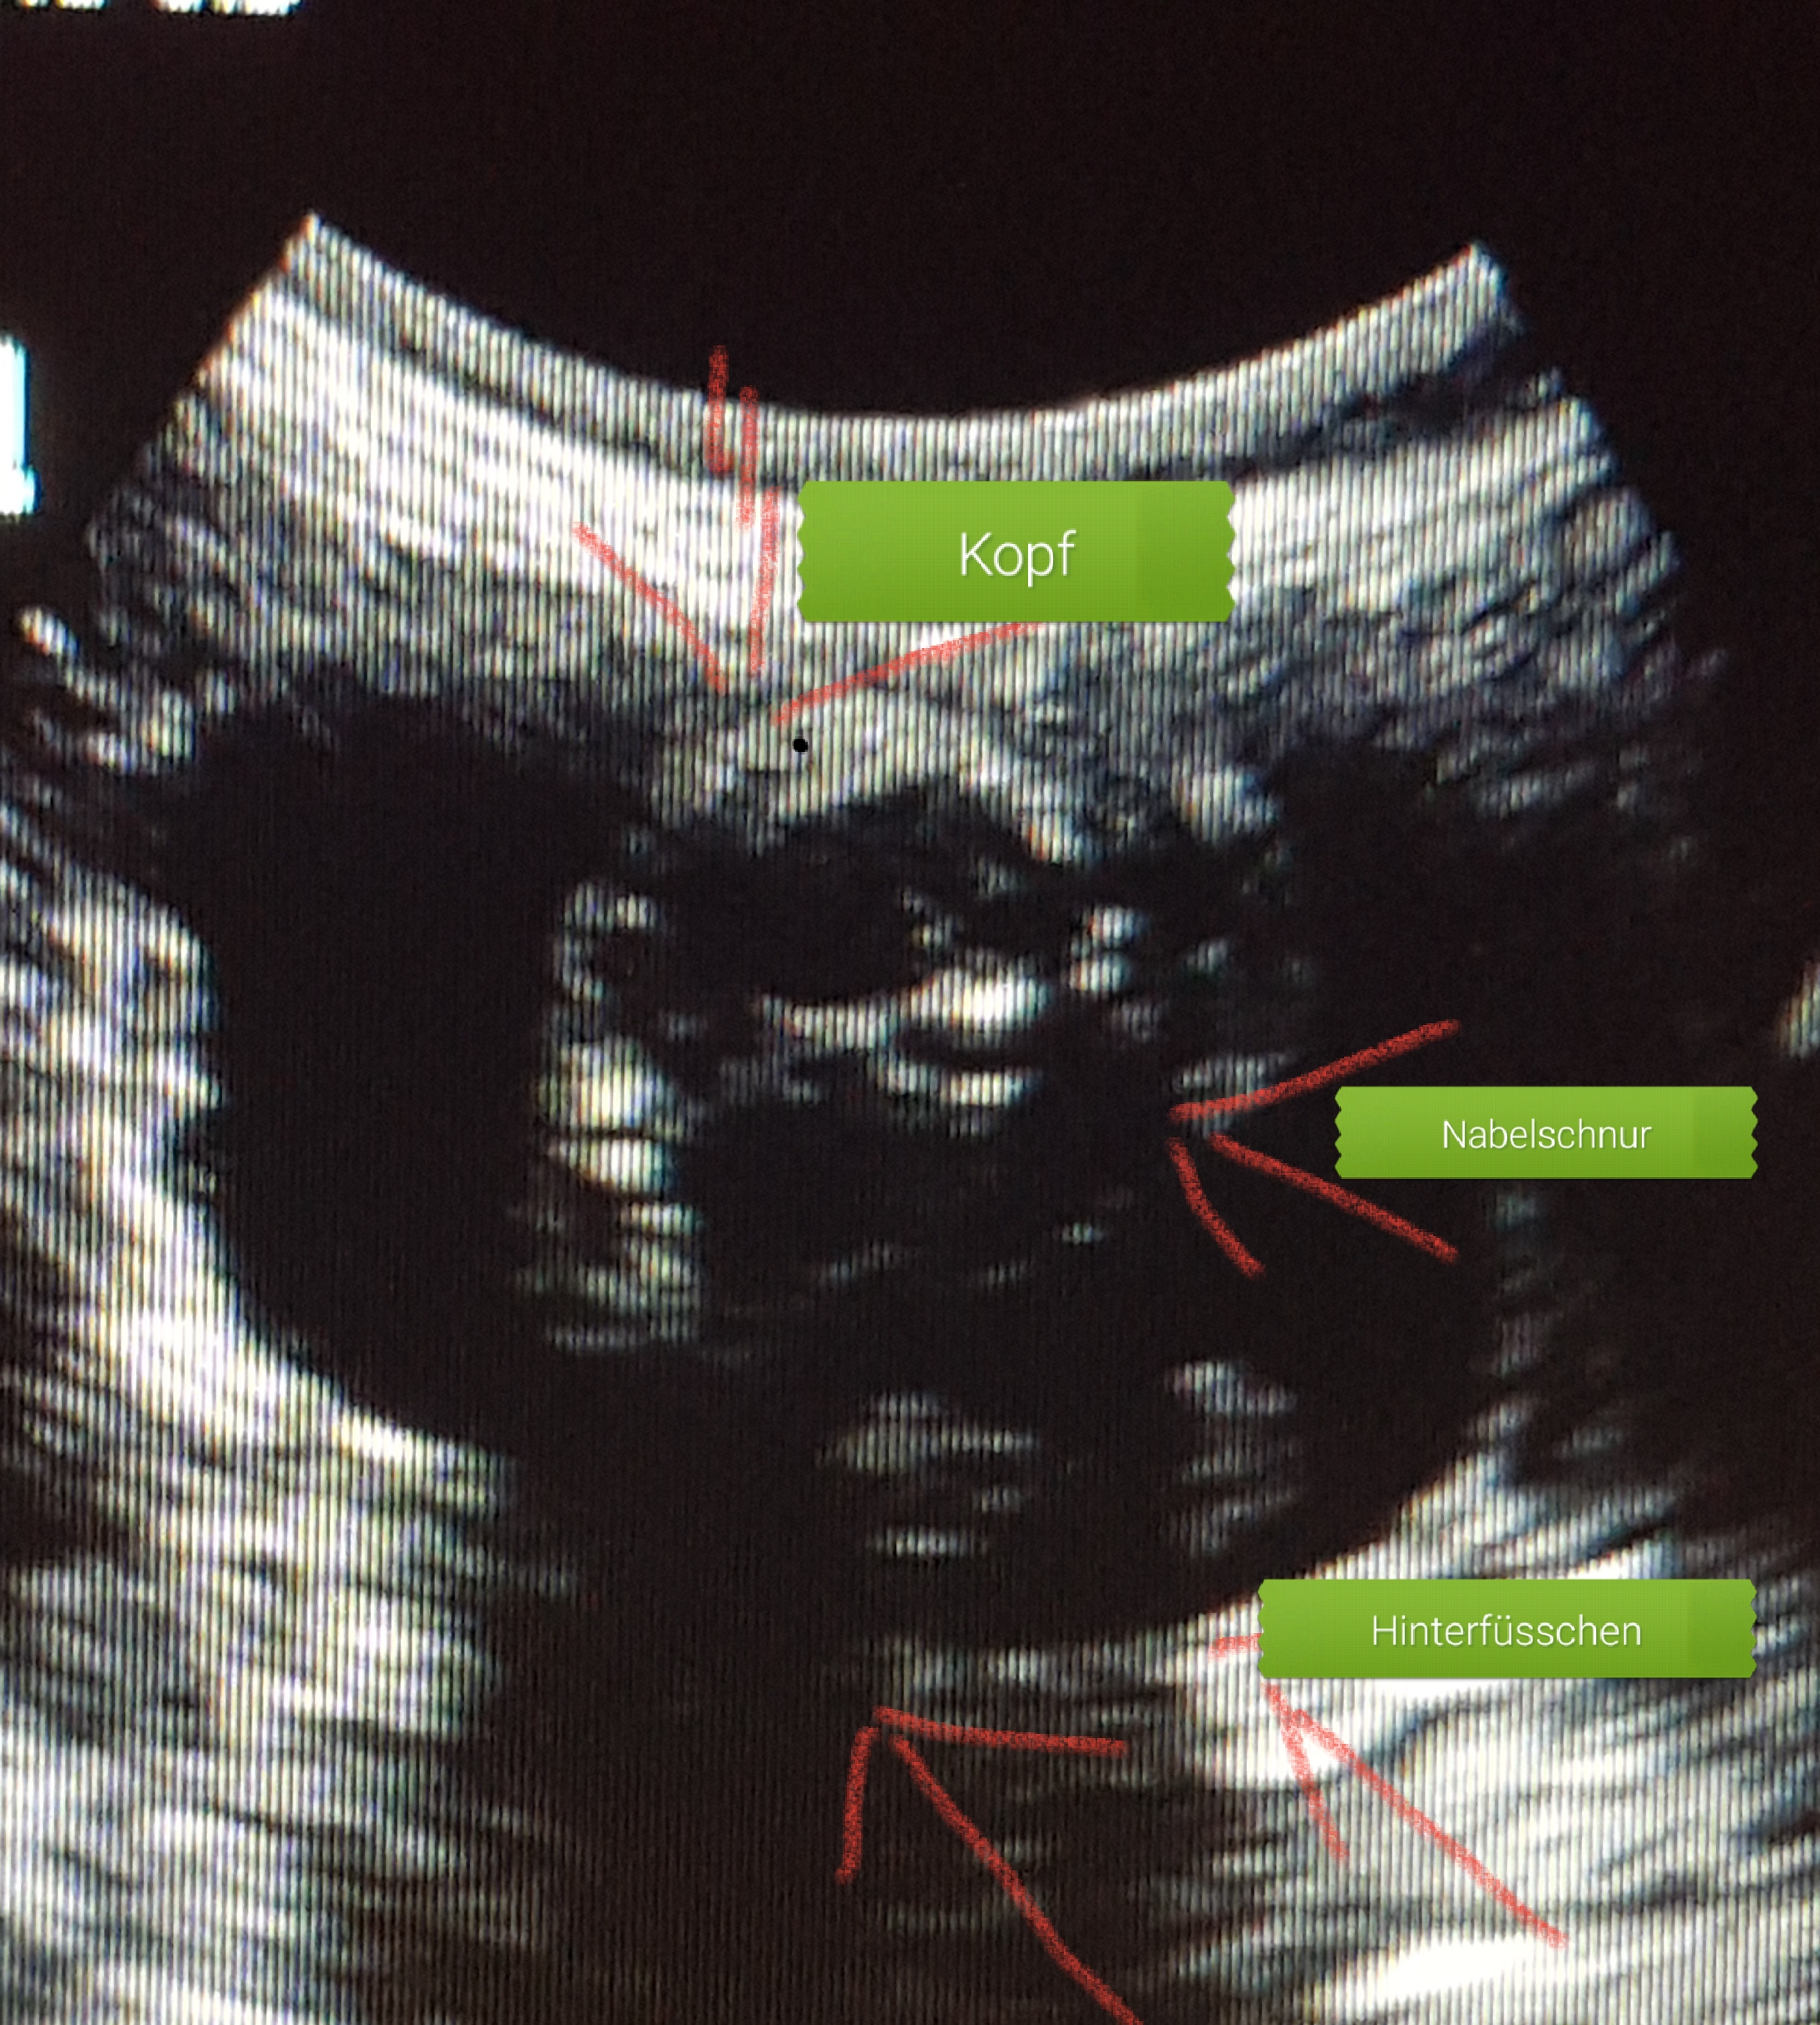

_Trächtigkeitsnachweiss/Ultraschall/ungefähre Anzahl

- Überprüfung von Vitalität und Wachstum

-Überwachung der Herztöne